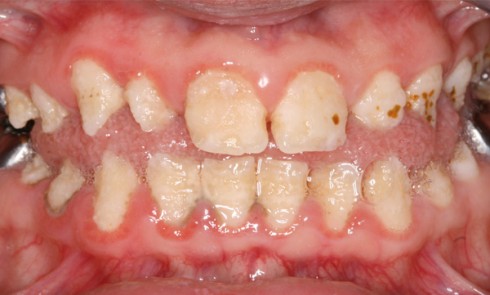

L’inclusion dentaire multiple est rare et est peu décrite dans la littérature scientifique [1]. Les étiologies les plus fréquentes de...